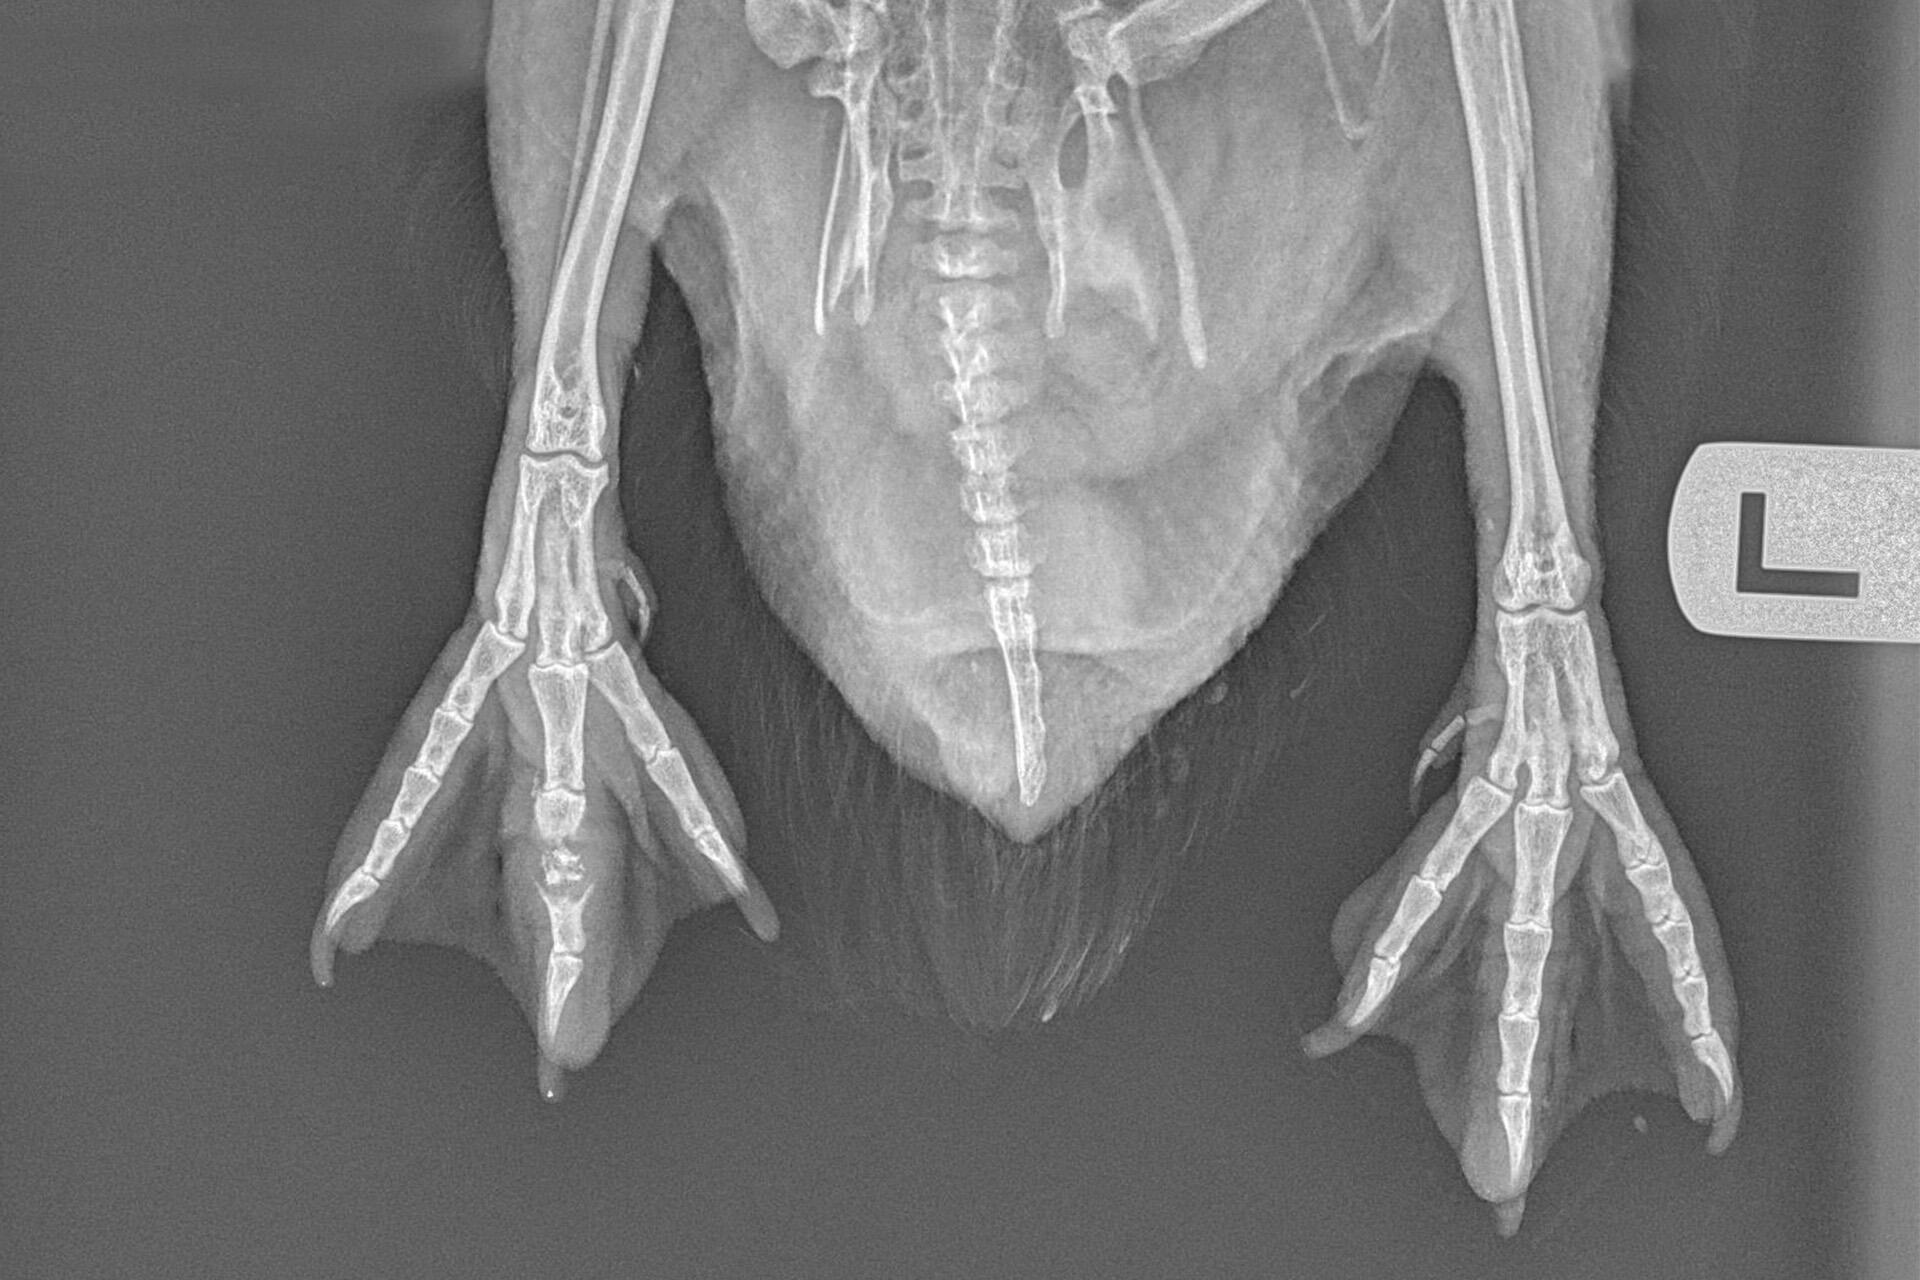

This kororā was very thin on arrival, with wounds on its body and right foot. It immediately received pain relief, antibiotics, antifungals and fluid therapy. Our vet team carried out an initial anaesthetic procedure once the penguin was stabilised, to assess the wounds and take blood tests and X-rays. These blood tests showed inflammation, but its kidneys and liver looked to be okay.

Due to the severity of these wounds and the presence of infection, this patient has needed multiple surgeries. To ensure there was no debris left inside, the wounds were decontaminated and debrided before stitching them up. The deepest part of the wound on the body was right up against the ribs, so we’re thankful for the penguin that it wasn’t any deeper.

Despite antibiotics, the wounds on the right foot developed a severe infection of the bone. A sample of the bacteria was taken and grown in the lab to look for antibiotic resistance and guide further treatment. If antibiotics did not work, the infected bone would have needed to be surgically removed. Thankfully, with the change in treatments, we have seen great improvement and the bone is slowly healing! We’re hopeful that over the next few weeks the bone will continue to heal and we can remove the splint which is in place to protect it.